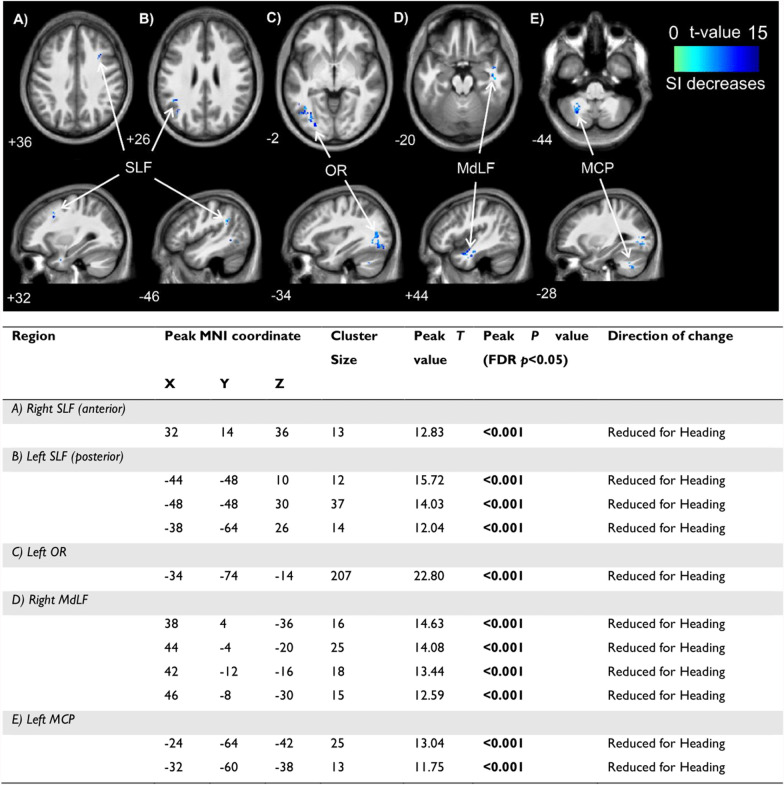

Results: Fifteen healthy male soccer players participated in a randomised, controlled, crossover pilot trial. The intervention was a non-concussive soccer heading task ('Heading') and the control was an equivalent 'Kicking' task. Participants underwent MRI scans ~ 45 min post-task which took ~60 min to complete. Blood was also sampled, and cognitive function assessed, pre-, post-, 2.5 h post-, and 24 h post-task. Brain chemistry: Heading increased total N-acetylaspartate (p = 0.012; g = 0.66) and total creatine (p = 0.010; g = 0.77) levels in the primary motor cortex (but not the dorsolateral prefrontal cortex) as assessed via proton magnetic resonance spectroscopy. Glutamate-glutamine, myoinositol, and total choline levels were not significantly altered in either region. Brain structure: Heading had no significant effects on diffusion weighted imaging metrics. However, two blood biomarkers expressed in brain microstructures, glial fibrillary acidic protein and neurofilament light, were elevated 24 h (p = 0.014; g = 0.64) and ~ 7-days (p = 0.046; g = 1.19) post-Heading (vs. Kicking), respectively. Brain Function: Heading decreased tissue conductivity in 11 clusters located in the white matter of the frontal, occipital, temporal and parietal lobes, and cerebellum (p's < 0.001) as assessed via electrical properties tomography. However, no significant differences were identified in: (1) connectivity within major brain networks as assessed via resting-state functional MRI; (2) cerebral blood flow as assessed via pseudo continuous arterial spin labelling; (3) activity within electroencephalography frequencies (infra-slow [0.03-0.06 Hz], theta [4-8 Hz], alpha [9-12 Hz], or beta [13-25 Hz]); or (4) cognitive (memory) function.